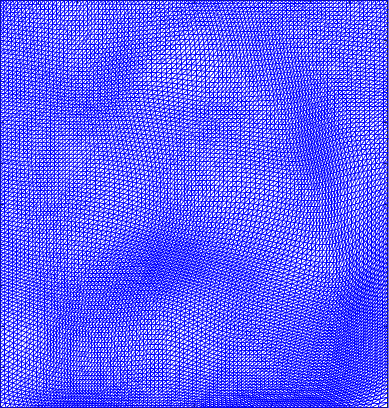

Figure 4 shows the visualisation of Figure 3 mappings in the form of grids. Let and be the Beltrami coefficients of the registration maps from the reference frame to the ground truth frame in Figure 3(a) and the perturbed frame in Figure 3(b) respectively. Figure 4(a) shows the mapping associated to Beltrami coefficient , and Fig 4(b) shows the mapping associated to BC . From Figure 4(c) and Fig 4(d), we can see that our method successfully restored the normal and abnormal deformation. Figure 4 serves as evidence that our decomposition is meaningful, in the sense that our method does not blindly return a Beltrami Descriptor with certain periodicity, but the decomposed descriptor does carry our desired information to recover the deformation to a large extent.